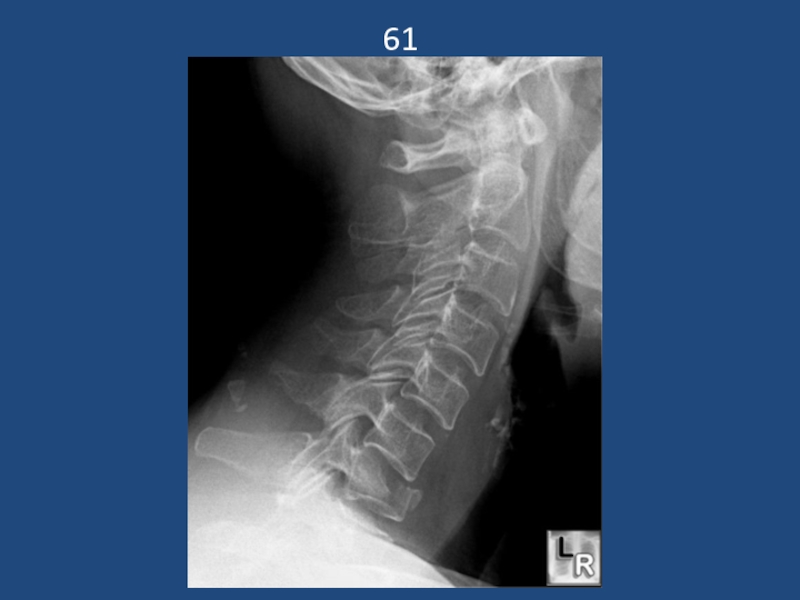

Слайд 1413

Подвывих с3 кпереди. Взрывной перелом с6

13Подвывих с3 кпереди. Взрывной перелом с6